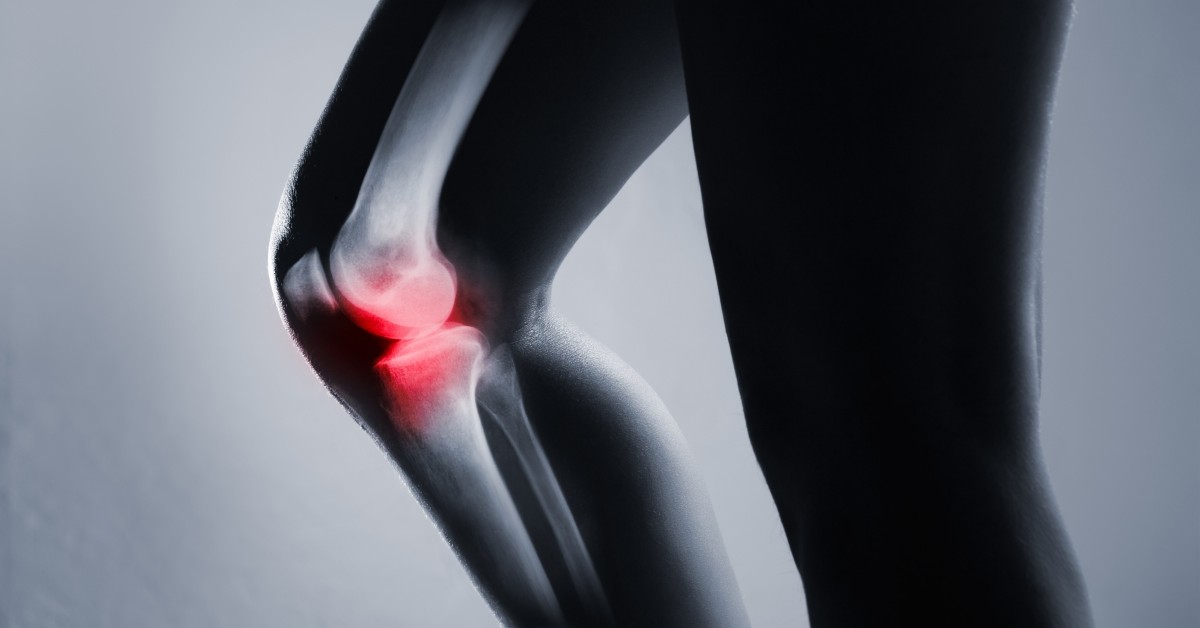

Unfortunately, osteoarthritis is a very common condition that affects more than 3 million people per year in the U.S. alone. This condition occurs when cartilage between joints begin to erode and the bones rub against each other. This can cause severe aches, sharp pain, and inflammation. Arthritis develops most often in the hands, neck, lower back, knees, hips, and shoulders, making normal movements uncomfortable or even impossible.

As we mentioned, arthritis is caused by a deterioration of cartilage between bone joints. While medication can dull the pain, it can lead to drug dependency and addiction. Physical therapy may help, but the discomfort will remain. Surgery is a drastic option and, while it may be a solution, your joint will never be your joint again.

This should cause a decrease in pain and inflammation as the cartilage builds back up and creates a buffer between bone joints.